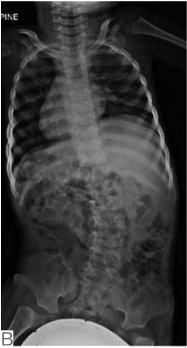

有研究报道,约20%~67%的先天性多发性关节挛缩症患者可出现脊柱侧凸。这类患者往往出生时就表现为脊柱畸形,反映出胎儿在母体宫内位置(图4)。在婴儿期脊柱侧凸进展很快,直至儿童后期才趋于稳定。大多数脊柱侧凸在5岁前可发现,对于肌发育不良及综合征型关节挛缩患者来说,胸弯及胸腰弯更多见,腰弯少见。对远端关节挛缩患者来说,胸腰弯更多见,此类患者侧凸进展比其他类型更快(图5)。

图4肌发育不良新生儿临床特征表现

A.显示明显脊柱侧凸,反应宫内胎位情况;B.同一小孩4岁时行平卧位X线提示腰段30°侧凸;C.同一小孩9岁时行平卧位X线提示腰段42°侧凸(引自Komolkin I, et al. Treatment of Scoliosis Associated With Arthrogryposis Multiplex Congenita.J Pediatr Orthop,2017, 37 Suppl 1:S24-S26.)